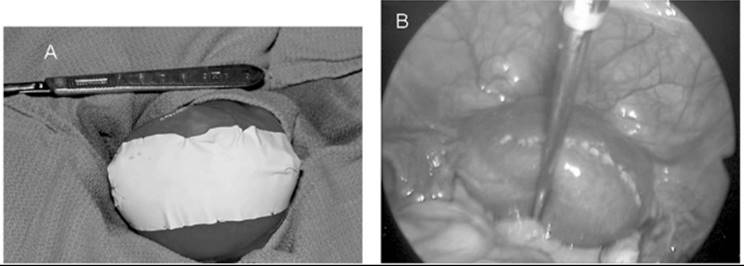

When symptomatic leiomyomata are not completely within the endometrial cavity but in an intramural location, an abdominal surgical approach usually is required. With infrequent exceptions, a low transverse incision yields adequate surgical exposure. Rarely, a vaginal myomectomy can be performed with proper patient selection, but this clinical situation is rare and requires a high degree of surgical skill. The goal of a myomectomy is to remove all the identifiable leiomyomata with the least possible alteration of the reproductive tract. There are numerous surgical techniques but, in general, the myometrium is incised, the myoma dissected from the surrounding myometrium, and the incision closed in layers with absorbable suture to ensure hemostasis and myometrial integrity (Fig. 49.5). Entry into the endometrial cavity is not associated with any significant morbidity, but it is essential not to place sutures though the endometrial cavity wall as if it is a layer to close. Because the distance to the opposite endometrial surface is small, approximating the myometrium underlying the endometrium to the corresponding opposite side is all that is necessary. Cervical fibroids can represent a significant surgical challenge because of their proximity to the bladder and ureters, as well as the difficulty attaining hemostasis. Similarly, parasitic fibroids can be difficult to remove depending on their vascular supply (Fig. 49.6).

FIG. 49.5. Myomectomy. A: Surgical exposure of a large uterus containing an intramural leiomyoma is depicted. The fibroid is dissected from the underlying myometrium in (B). C: The uterine incision is extended down into the cavity and the fibroid is removed. The myometrium is reapproximated in layers (D) and the uterine muscle wall closed.

FIG. 49.6. A parasitic fibroid. A large tumor has become parasitic to a loop of small bowel, deriving its blood supply from the new vascular source. This typically happens only with large posterior or fundal tumors and is more common when they are pedunculated. The mechanism is felt to be pressure necrosis and revascularization during healing of the necrosis of the bowel wall.